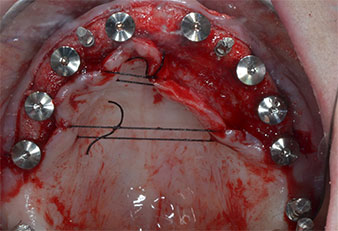

Due to the relatively hard bone (D2) in this area, the 10 mm long implant sites at positions 11 and 21 were finalized with a 4 mm diameter rotary drill, in combination with a W&H WS-75 L surgical contra-angle handpiece, the W&H Implantmed implant motor and the optional W&H Osstell ISQ module. In contrast, due to the soft bone the posterior sites were prepared to a final 3 mm diameter using the Piezomed I3P instrument. The implants were finally placed transgingivally to osseointegrate for three months (Figs. 6-10). The existing denture was retained on four provisional implants (Fig. 8).

10-mm tissue level implant

Fig. 6: A 10-mm tissue level implant is placed at position 21. The implant at position 11 and the three left posterior 4-mm implants are already in place.

Implant stability

Fig. 7: Implant stability is determined with a SmartPeg and the W&H Osstell ISQ module. All values are in the medium to high range, with a minimum of ISQ 69.

Provisional implants

Fig. 8: After fixation of the gingiva formers provisional implants are placed at positions 18, 12, 22 and 28.